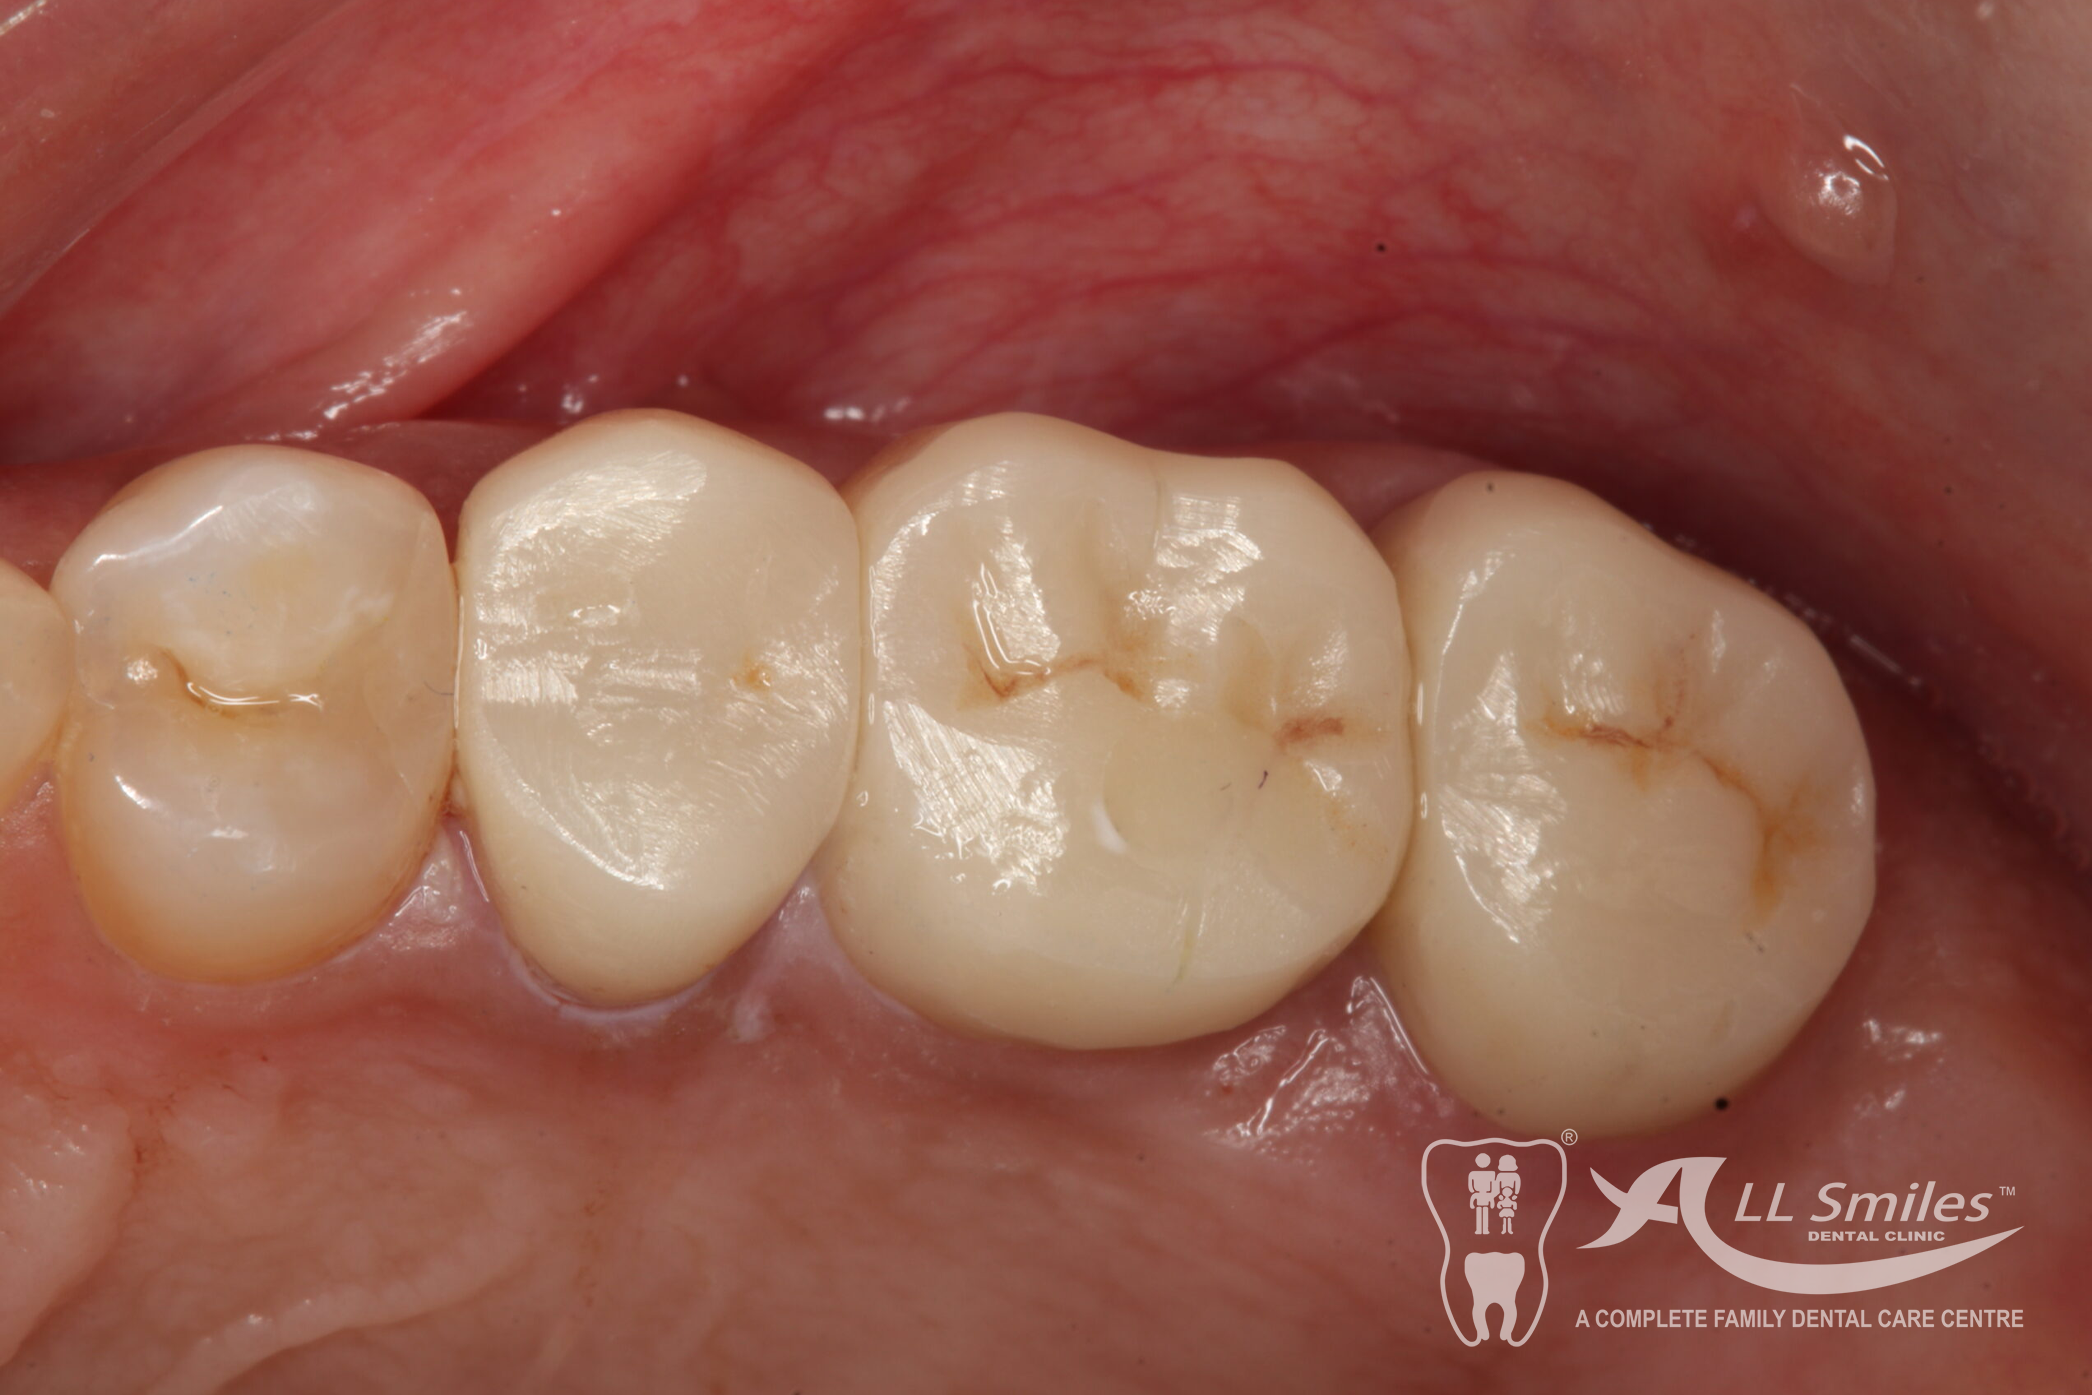

Dental Implants Gallery